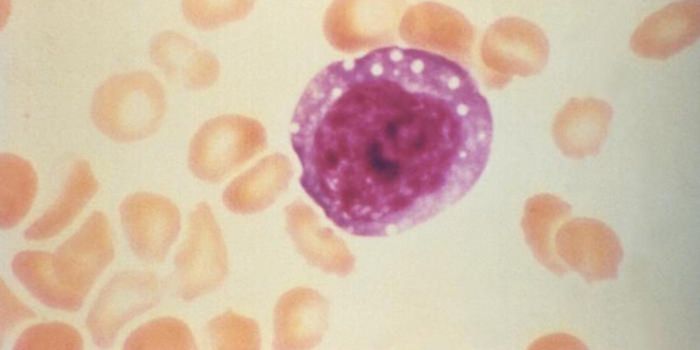

JUL 08, 2021Genetics & GenomicsChildren with Down syndrome have a significantly higher likelihood myeloid leukemia occurring in the first five years of ...